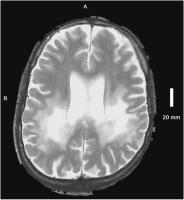

Abbildung 2: Koronale TIRM: Ausdehnung der Hyperintensitäten bis zur Subkortikalregion.

Keywords:

Adrenomyeloneuropathie

,

Hyperintensität

MRT

Neurologie

Subkortikalregion